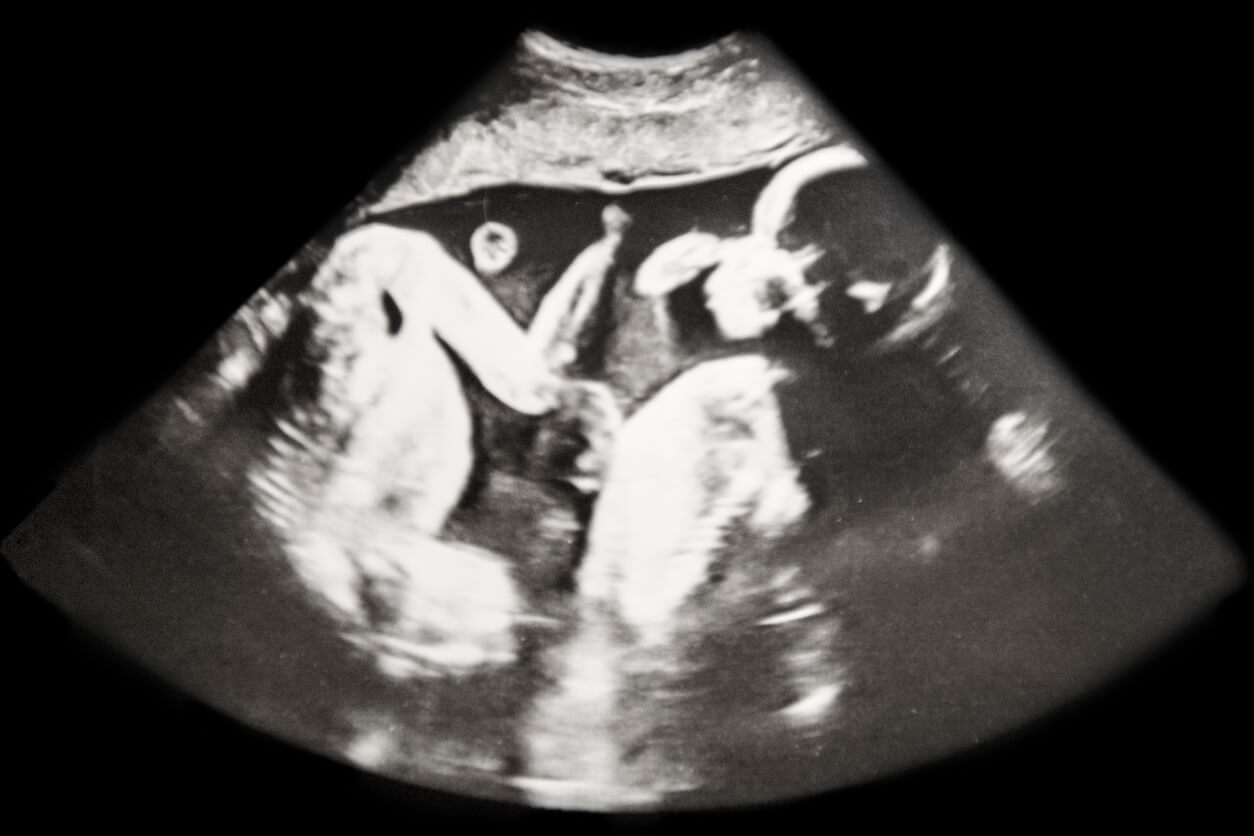

La dysplasie de la hanche touche un grand nombre de bébés dans le monde. Cependant, la cause exacte qui la génère n’est pas encore connue. Actuellement, on l’appelle aussi dysplasie développementale de la hanche, car elle survient au stade intra-utérin ou dans les moments proches de la naissance.

La dysplasie développementale de la hanche (DDC) est l’une des pathologies les plus fréquentes chez le nouveau-né et peut survenir entre la 11e semaine de gestation et l’âge de deux ans.

Cette condition est plus fréquente dans les grossesses multiples, en particulier dans la première grossesse. Elle survient le plus souvent du côté gauche et son intensité est variable : de l’instabilité articulaire légère à la luxation complète de la hanche.